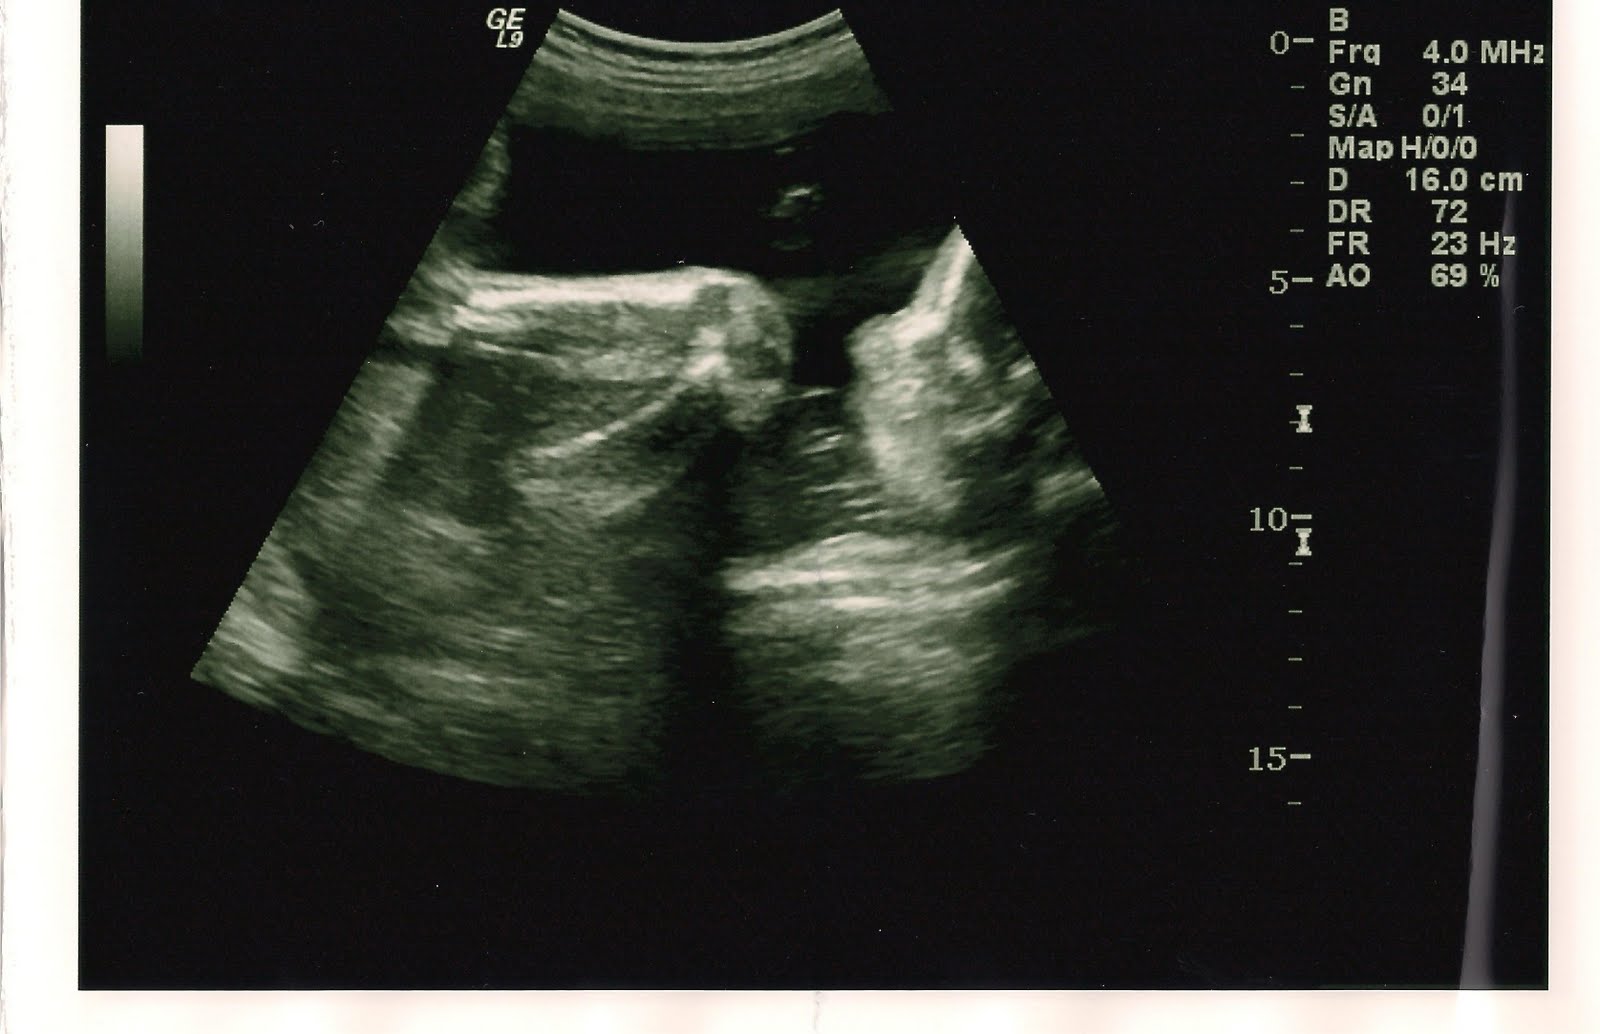

I just realized we never posted that Mason is having a little brother! I guess we've had a few adventures to distract us from this post. I've had two ulrasounds this last month, and here they are! My ultrasound tech likes to type comments on the prints. She's funny. My babies don't like to pose for the cameras the way the techs wish they would, and they just couldn't get images of things they wanted to see, like the connection of the umbilical cord to his body. But, I don't mind going in multiple times to see him. I love being able to watch him move around while I feel him at the same time.

These were taken 28 March 2011- (profile pics looking up for those who can't tell)